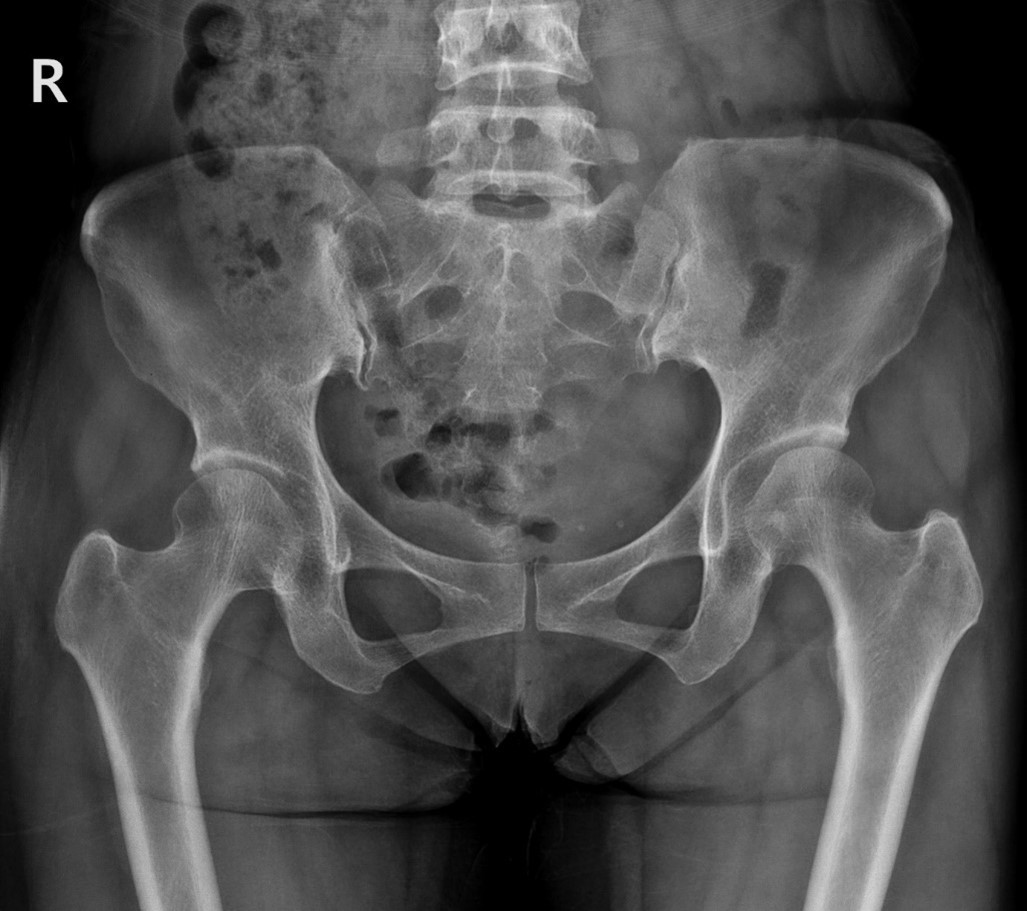

MRI 촬영 결과 허리디스크 진단을 받으셨다고 하시더군요.

그림2.jpg 촬영 일시: 2025.03.29

<Fig 1. 이상 소견 없는 X-Ray>